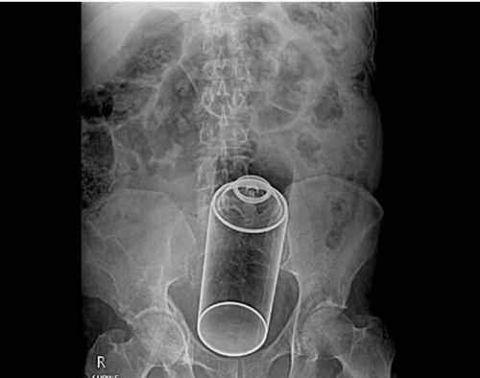

手机不够了,录音带也可以